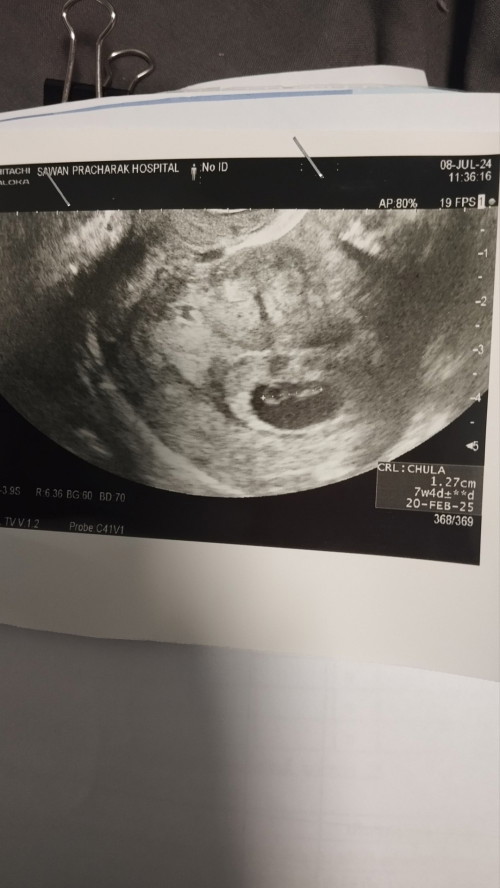

คุณแม่ซาวด์เจอน้องเจอหัวใจน้องอยู่ที่กี่วีคกันหรอคะ

7+4 พร้อมเสียงหัวใจค่า